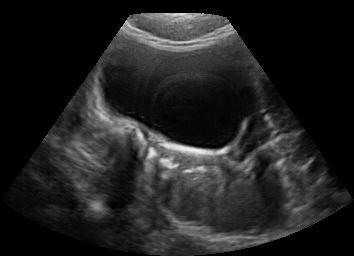

Real in-vivo images. 22 ultrasound sequences were collected using a GE Voluson E8 machine during standard fetal screening exams of 8 patients. Each sequence is several seconds long. We extracted all 4427 frames and resize them to , see Fig. 2 for some examples. The resulting image set was randomly split into training-validation-test sets by a 80-10-10% ratio.